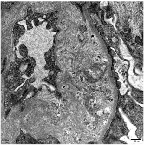

肾穿刺活检结果“一锤定音”,通过光学显微镜(光镜)和电子显微镜(电镜)再次明确诊断,均证实了肾内血栓性微血管疾病的特征性改变。李女士最终被明确诊断为非典型溶血性尿毒综合征(aHUS)。

肾脏TMA电镜表现